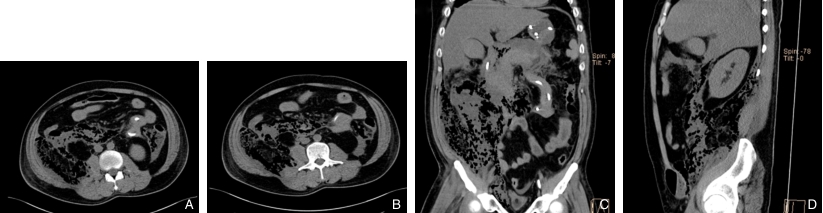

图1 早发广泛性EP的CT图像(胰周、双侧结肠旁及右侧腹膜后间隙、右下腹前壁组织及右侧腹股沟管内大量积气,呈蜂窝状改变) A-B:横断位;C:冠状位;D:矢状位Fig.1 CT images of early-onset extensive EP (showing massive gas accumulation in the peripancreatic area, bilateral paracolic gutters, right retroperitoneal space, right anterior abdominal wall, and right inguinal canal, forming a honeycomb pattern) A-B: Axial view; C: Coronal view; D: Sagittal view